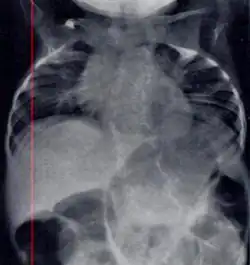

| Radiograph depicting typical skeletal features of Jarcho-Levin syndrome, subtype spondylothoracic dysplasia. Note fanlike configuration of the ribs, with extensive posterior fusion, along with multiple vertebral segmentation defects. | |

Spondylocostal dysostosis, also known as Jarcho-Levin syndrome (JLS), is a rare, heritable axial skeleton growth disorder. It is characterized by widespread and sometimes severe malformations of the vertebral column and ribs, shortened thorax, and moderate to severe scoliosis and kyphosis. Individuals with Jarcho-Levin typically appear to have a short trunk and neck, with arms appearing relatively long in comparison, and a slightly protuberant abdomen. Severely affected individuals may have life-threatening pulmonary complications due to deformities of the thorax. The syndrome was first described by Saul Jarcho and Paul M. Levin at Johns Hopkins University in 1938.[1]

Spondylothoracic dysplasia

Spondylothoracic dysplasia, or STD, has been repeatedly described as an autosomal recessively inherited condition that results in a characteristic fan-like configuration of the ribs with minimal intrinsic rib anomalies. Infants born with this condition typically died early in life due to recurrent respiratory infections and pneumonia due to their restricted thorax.[3][4][5] Recently, a report[6] has documented that actual mortality associated with STD is only about 50%, with many survivors leading healthy, independent lives.

In contrast to STD, the subtype spondylocostal dysostosis, or SCD features intrinsic rib anomalies, in addition to vertebral anomalies. Intrinsic rib anomalies include defects such as bifurcation, broadening and fusion that are not directly related to the vertebral anomalies (such as in STD, where extensive posterior rib fusion occurs due to segmentation defects and extreme shortening of the thoracic vertebral column).[6] In both subtypes, the pulmonary restriction may result in pulmonary hypertension, and have other potential cardiac implications.[7]